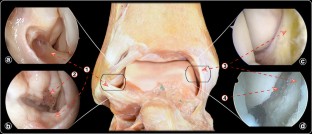

During diagnostic arthroscopy, 12 patients showed an isolated anterior talofibular ligament (ATFL) injury, and in one patient, both the ATFL and calcaneofibular ligament were affected. Arthroscopic examination of the deltoid ligament demonstrated a tear affecting the anterior area of the ligament in all cases. The tear was described as an "open book" tear, because the ligament was separated from the medial malleolus when applying passive internal rotation of the tibio-talar joint. This gap was closed when the tibio-talar joint was in neutral rotation or externally rotated. All patients reported subjective improvement in their ankle instability after the arthroscopic all-inside ligaments repair. The median AOFAS score increased from 70 (44–77) preoperatively to 100 (77–100) at final follow-up.

Fig. 3